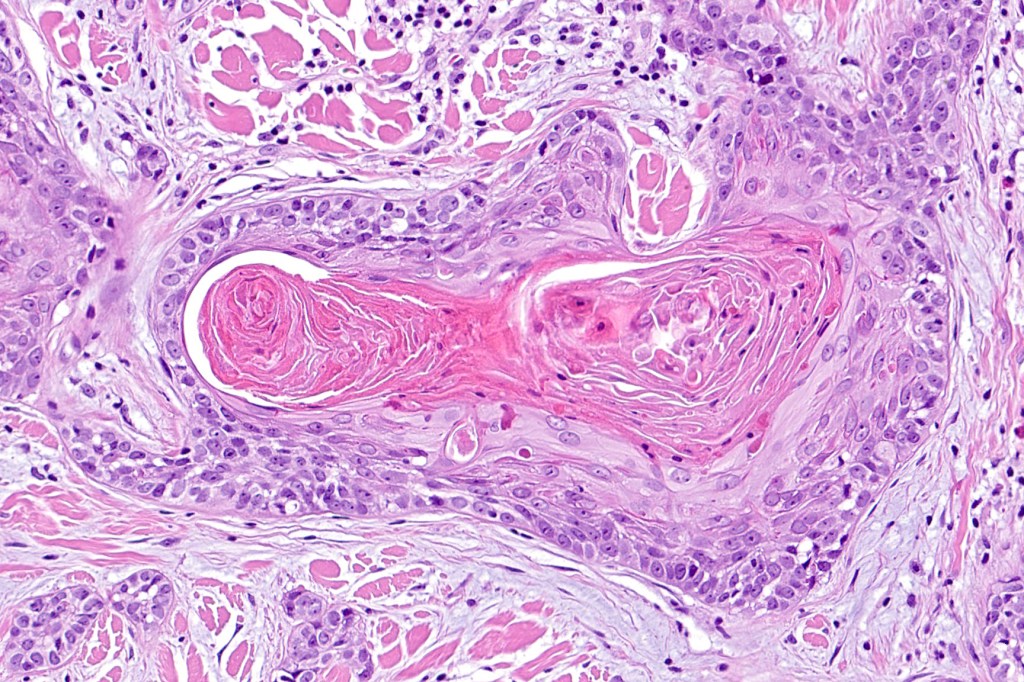

•Widely infiltrating biphasic tumor

•Superficial SCC

•Adenocarcinoma in deeper reaches

•Deep part may show both ducts and glands

•Often extends to the subcutaneous fat